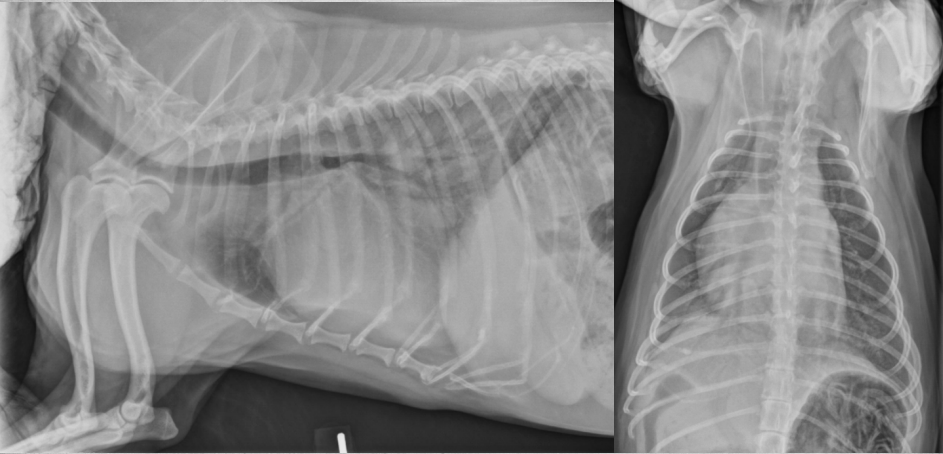

● 2 yo Labrador

● Ingested laundry detergent the day

before

black hole is bifurcation

air bronchograms visible -> alveolar pattern

lobar sign in lower VD image

aspiration pneumonia -> chemical burn in the lungs secondary to laundry detergent aspiration